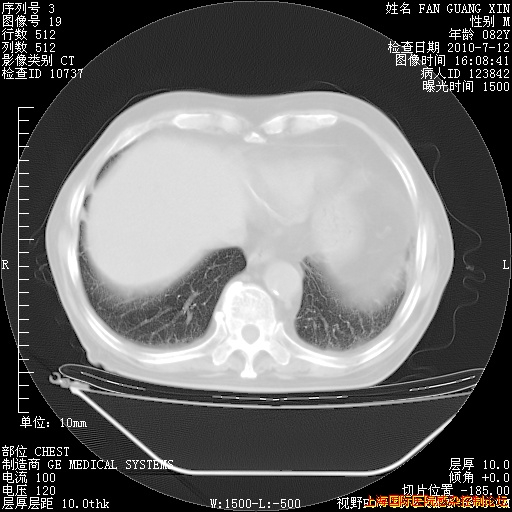

今天CT

整整相隔30天的肺部CT好像有所好转啊。甲强龙减量第3天,需要观察体温。

海管,自昨日你和我通完话后,不知您岳父消化道症状有无缓解?体温怎样?阅读7.12日胸部ct,个人认为目前激素治疗是有效的,甲强龙减量是适宜的。因在抗痨治疗,需密切观察肝功、肾功能和血常规。不过,老年、长期住院和大量使用激素,很担心菌群失调发生